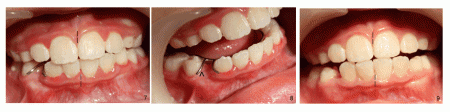

四個月後,下牙相當整齊了(圖三),在中切牙(1)與乳尖牙(C)之間放置一個彈簧(箭頭),為錯位的側切牙創造空間。一個月後,空間有所增加(圖四),但是之後進展緩慢,最後發現乳尖牙鬆動,不得不拔除(圖五),這樣側切牙就有足夠空間移動,三個星期,初見成效(圖六)。不久側切牙就位,最後為尖牙創造空間,去除矯正器,下前牙整齊(圖七),上下中線在一條線上(虛線),為了鞏固勝利成果,安裝固定維持器(圖七、圖八),其中一部分固定尖牙空間(圖八箭頭)。五個月後,維持器鬆動,本來應該重新固定,但是Alice母親不同意,不過牙齒還沒有移位,中線仍正常(圖九虛線)。